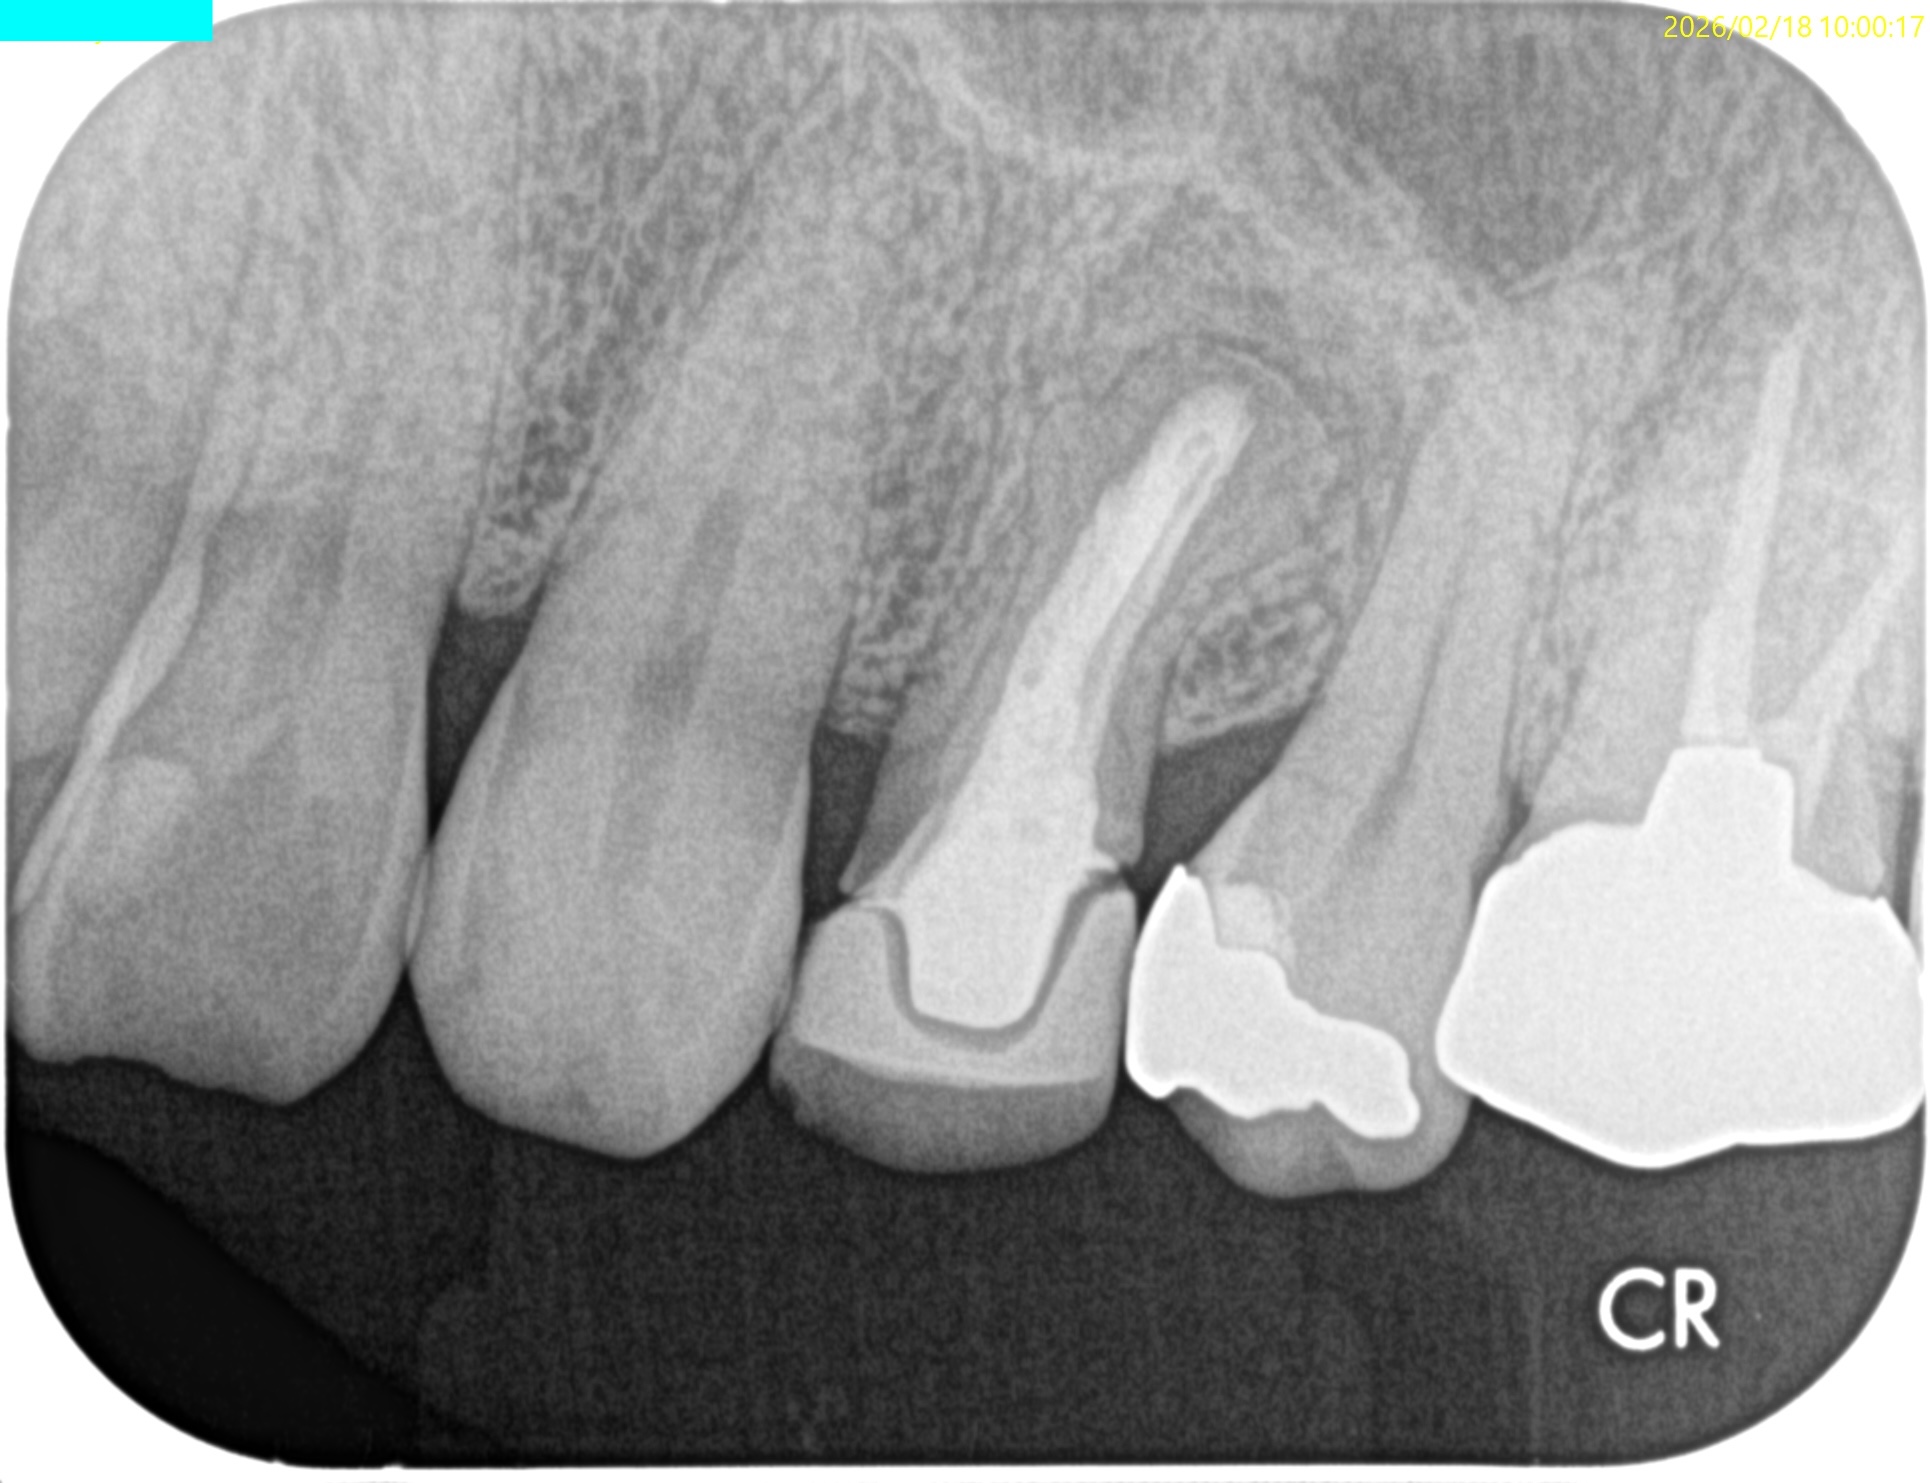

#12 Apicoectomy 6M recall(2026.2.18)

初診時と比較した。

問題は大きく解決している。